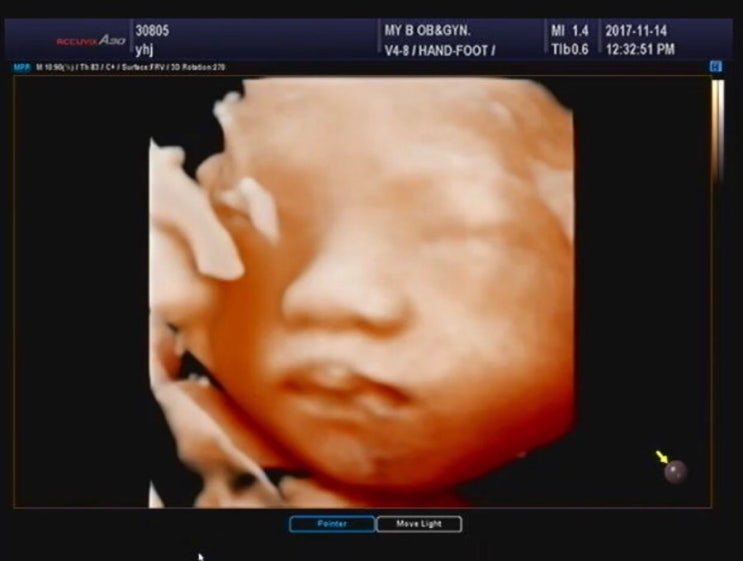

28주~ 35주 임신기록 및 입체초음파, 막달검사 ,주수사진기록

임신초기 확인한게 어제같은데 벌써 .... 제가 35주가 되었네요 ㅋㅋㅋㅋ 시간이 넘나 빨라서 무서워진다는...